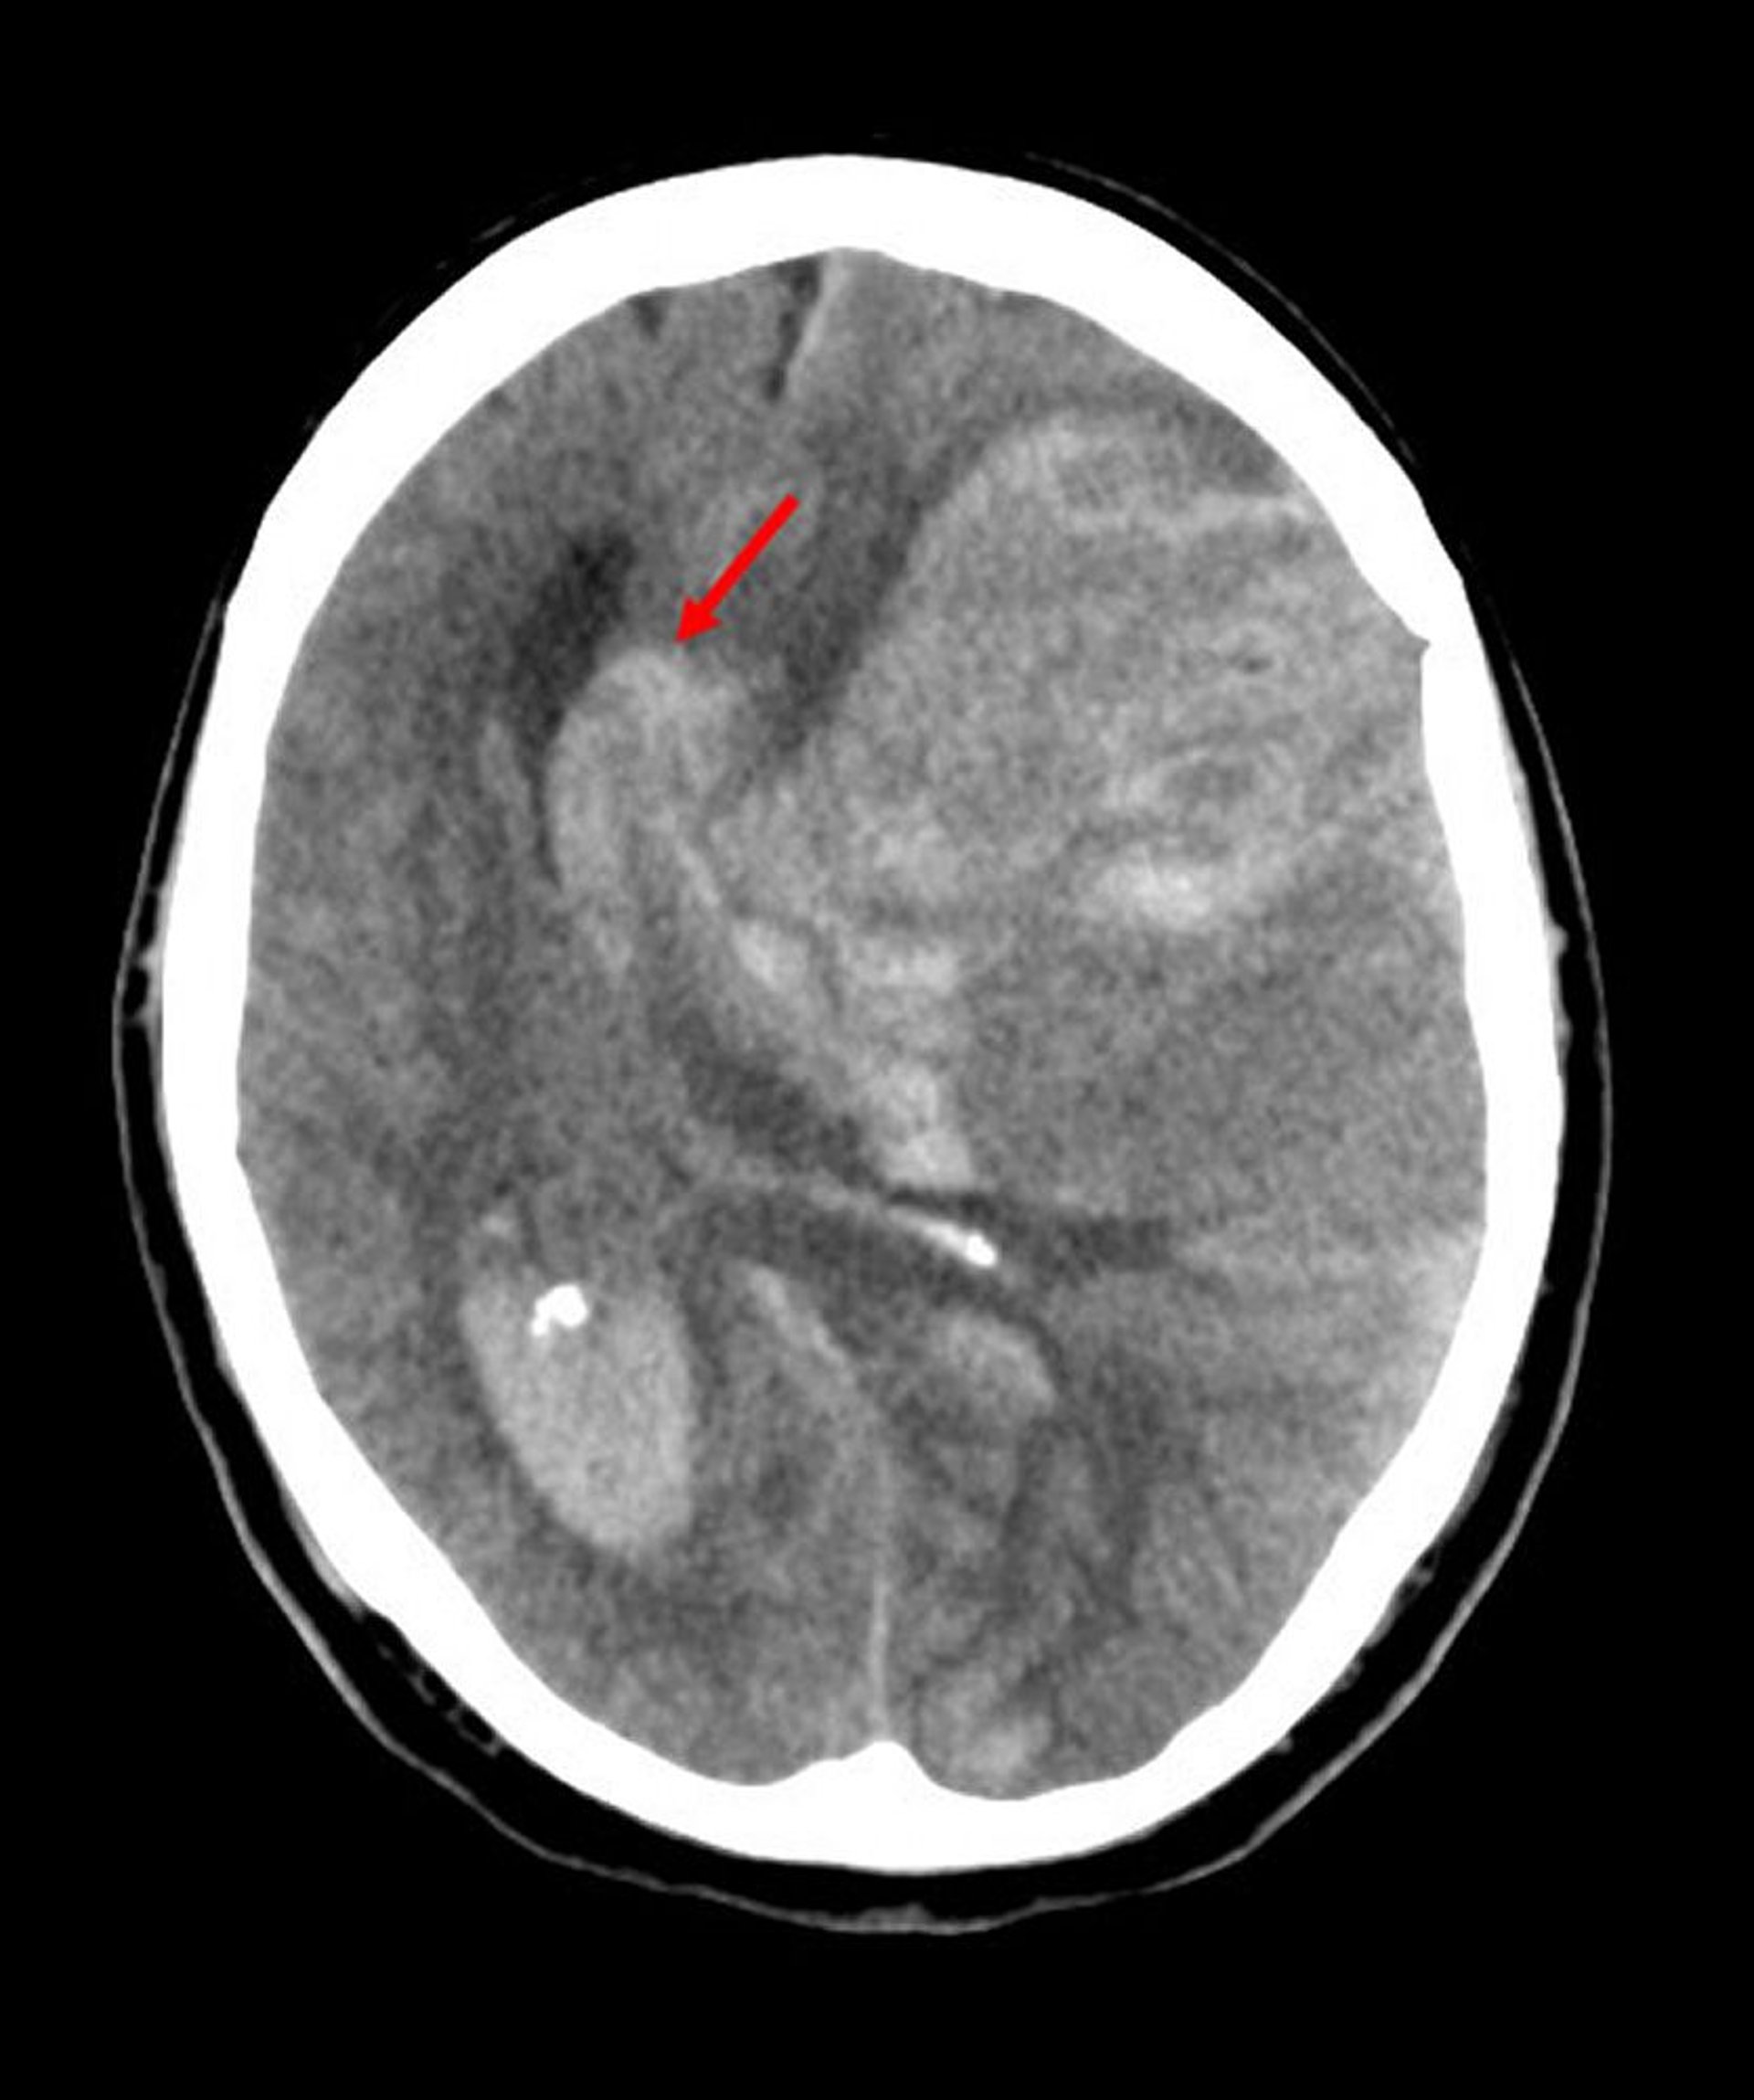

Подсерповидное (субфальксное) вклинение

Субфальксное вклинение – наиболее распространенный тип вклинения головного мозга. На данном изображении в левом полушарии головного мозга под свободным краем серповидного отростка (стрелка) имеется грыжа, возникшая вследствие повышенного внутримозгового давления, вызванного кровоизлиянием из-за инфаркта в бассейне средней мозговой артерии.